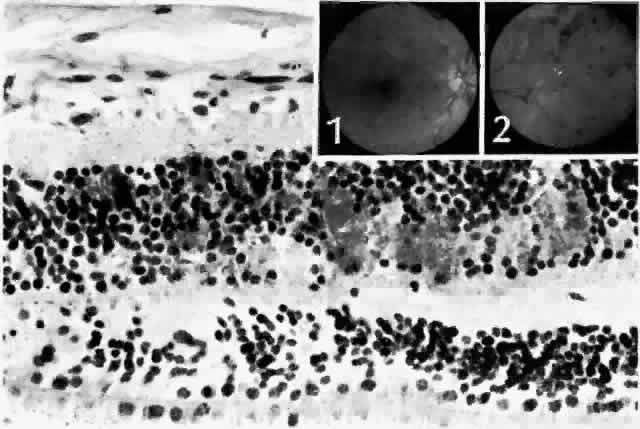

| Patients with diabetes may have tiny pinpoint iris transillumination defects. This

the iris pigment epithelium (Fig. 2; Color Plate 1,* Color Fig. A).18 These vacuoles contain glycogen. Some authors have found that the vacuolization

is transient, and thus related to blood glucose levels prior

to death,19 whereas others have been less convinced of such a relationship.20 See Color Plate 1 for Color Figs. A through G These glycogen vacuoles can rupture when the intraocular pressure is suddenly reduced, resulting in a cloud of pigment granules carried anteriorly in the aqueous fluid. This pigment may then be phagocytosed by the corneal endothelium. The pupils of patients with diabetes often dilate poorly, and the amount of glycogen in the pigment epithelium may correlate to damage to the dilator muscle. Rubeosis iridis is a clinical term for the reddish discoloration imparted by neovascularization of the iris surface. It is associated most frequently with retinal ischemia and neovascularization, and indicates the presence of a diffusible vascular proliferative factor secreted by the retina.21 Initially, the vessels can be quite difficult to see. With more advanced rubeosis, there may be ectropion uveae, an eversion of the posterior iris surface at the pupil margin. The earliest location of the new vessels has been a matter of longstanding debate. They appear at the pupil margin and in the angle virtually simultaneously, subsequently spreading across the iris surface, but gonioscopic examination is required for the vessels to be seen in the angle. In some patients, the vessels do form in the angle before being perceptible at the pupil margin.22 Peripheral anterior synechiae form rapidly after neovascularization of the iris, closing off the trabecular meshwork and giving rise to so-called neovascular glaucoma, which is difficult to treat. In addition, the vessels and associated fibrous tissue can proliferate across the pupil, sequestering it. Particularly in aphakic patients, the vessels can also extend through the pupil and onto the posterior iris surface. Histologically the new vessels are located anterior to the anterior border layer of the iris (Fig. 3, Color Fig. B). They are thin-walled, unlike the normal thick-walled iris stromal vessels. New vessels may be located only at the pupillary margin and in the angle at the iris root, corroborating the clinical finding.18 Scanning electron microscopy has disclosed a thin, transparent layer of myofibroblastic proliferation anterior to the new vessels. This explains the clinical observation that the anterior iris surface appears smoothed out, with loss of the collarette and crypts typically seen on the normal iris surface. Myofibroblasts have contractile properties and thus may be responsible for the angle closure of neovascular glaucoma and also for the eversion of the posterior iris surface at the pupillary margin (Color Fig. C).23 |